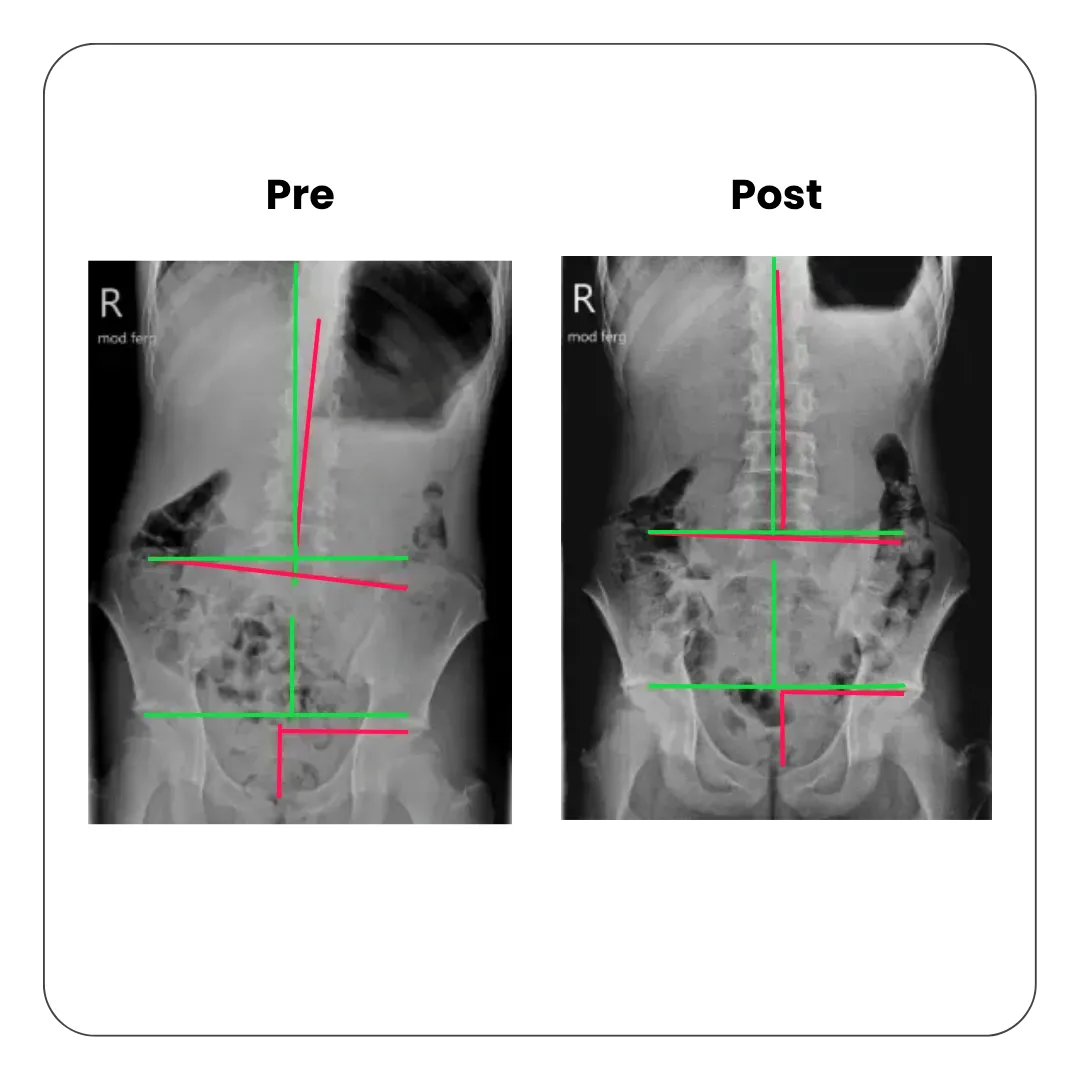

Correcting Lumbar Deviation & Managing Scoliosis

A misaligned lower spine affects mobility, nerve communication, and overall posture. In- depth examination and x-rays will determine if the deviation is due to a short leg, a postural issue, an idiopathic scoliosis or a congenital anomaly. Our CBP approach realigns the lumbar region by correcting the cause to support a healthier spine and nervous system.

Pre and post X-ray comparison showing lumbar spine alignment improvement in scoliosis care